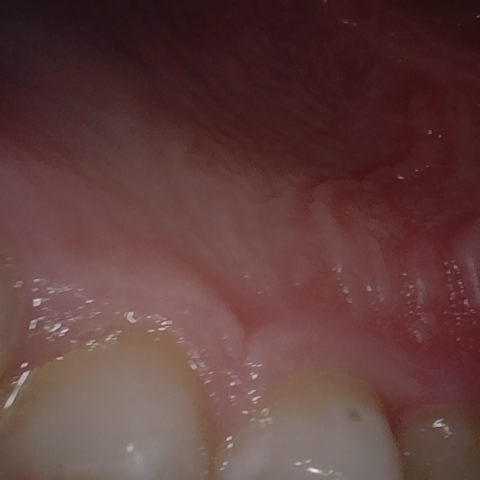

Annotated as "Good"